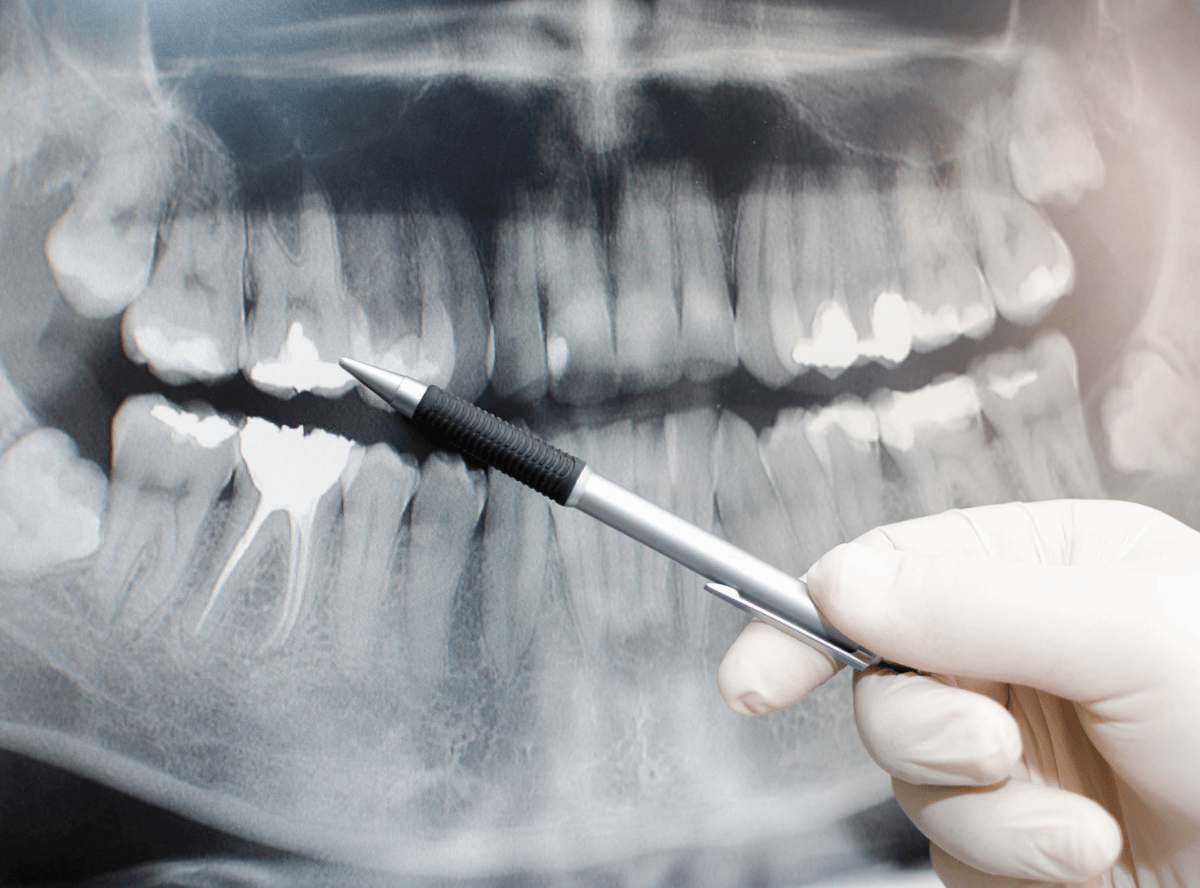

そもそも、レントゲン写真で何を見ているのか?

歯医者さんで「レントゲン撮りますね」と言われたこと、ありますよね。

でも、「あの白黒の写真でいったい何を見ているのか?」って、思わないですか?

実は、あのレントゲン写真には肉眼では見えない虫歯のヒントがたくさん隠れています。

レントゲン写真は、虫歯の診断の第一選択といえる、重要な診断材料です。

レントゲンって、どういう仕組み?

レントゲン(X線写真)は、体の中を「X線」という光でスキャンして、歯の内側や骨の様子を映す写真です。

・歯や骨のように硬いものは白っぽく写る

・虫歯や膿(うみ)など柔らかくなった部分は黒っぽく写る

この「白」と「黒」のコントラストで、我々歯科医師は、虫歯の有無や進行具合を見極めています。

レントゲンでチェックしているポイント

① 歯と歯の間に黒い影がないか

レントゲンで、歯に「黒い影」があれば、それが虫歯の可能性が高い。

また、影の濃さ・広がり具合で、虫歯の深さや大きさを診断します。

② 神経に近い虫歯かどうか

虫歯が歯の神経(歯髄:しずい)に近づいているかどうかも、レントゲンで判断。

神経まで到達していると、「神経を取る治療」が必要になることもあります。

③ 詰め物や被せ物の下に虫歯がないか

過去に治療した歯でも、詰め物のすき間から虫歯が再発することがあります。

これを二次カリエスといいます。

④ 根っこの先に膿(うみ)がたまっていないか

歯の根の先に白くぼやっとした影がある場合、歯の根の病気(根尖病変:こんせんびょうへん)が疑われます。

⑤ 歯の周りの骨の状態

歯周病になると、歯を支える骨が減っていきます。

レントゲンでは骨の高さがチェックできます。